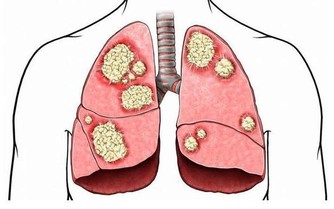

悲傷時傷“肺”

人在強烈悲哀時,會出現呼吸頻率改變、乾咳、氣短、音啞等症狀。

現代醫學則發現,悲傷時,人體交感神經系統分泌出大量壓力激素,增加心髒病發作風險。